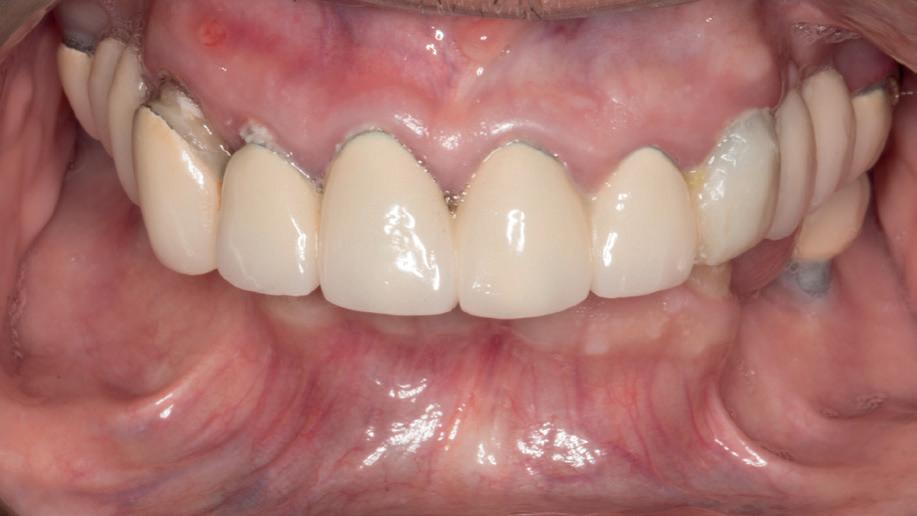

SITE AUGMENTATION Reconstituirea țesutului moale periimplantar și papilar în zona estetică

RECONSTITUIREA țesuturilor moi periimplantare. Scopul acestui raport de caz este de a demonstra procedurile chirurgicale utilizate pentru corectarea unui defect al țesuturilor moi periimplantare folosind țesutul moale interdentar în combinație cu tuberozitatea ca locație donatoare de țesut conjunctiv, utilizând o abordare prin tunelizare într-o zonă estetică.